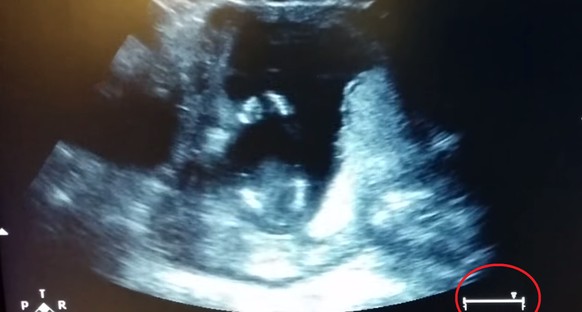

14 Wochen alt ist dieser Winzling, als er im Bauch der Mutter plötzlich zu klatschen beginnt. Also stimmen die Mama und ihr Arzt ein Lied an und dem Baby scheint das mächtig zu gefallen – es gibt mit seinen kleinen Händchen weiter den Takt an.

Und womöglich hat die Dame recht. Sieht man sich den Balken links auf dem Bildschirm an, bewegt sich der Regler immer hin und zurück. Aber selbst wenn hier herumgedoktert wurde, einmal hat das Baby ganz sicher geklatscht.